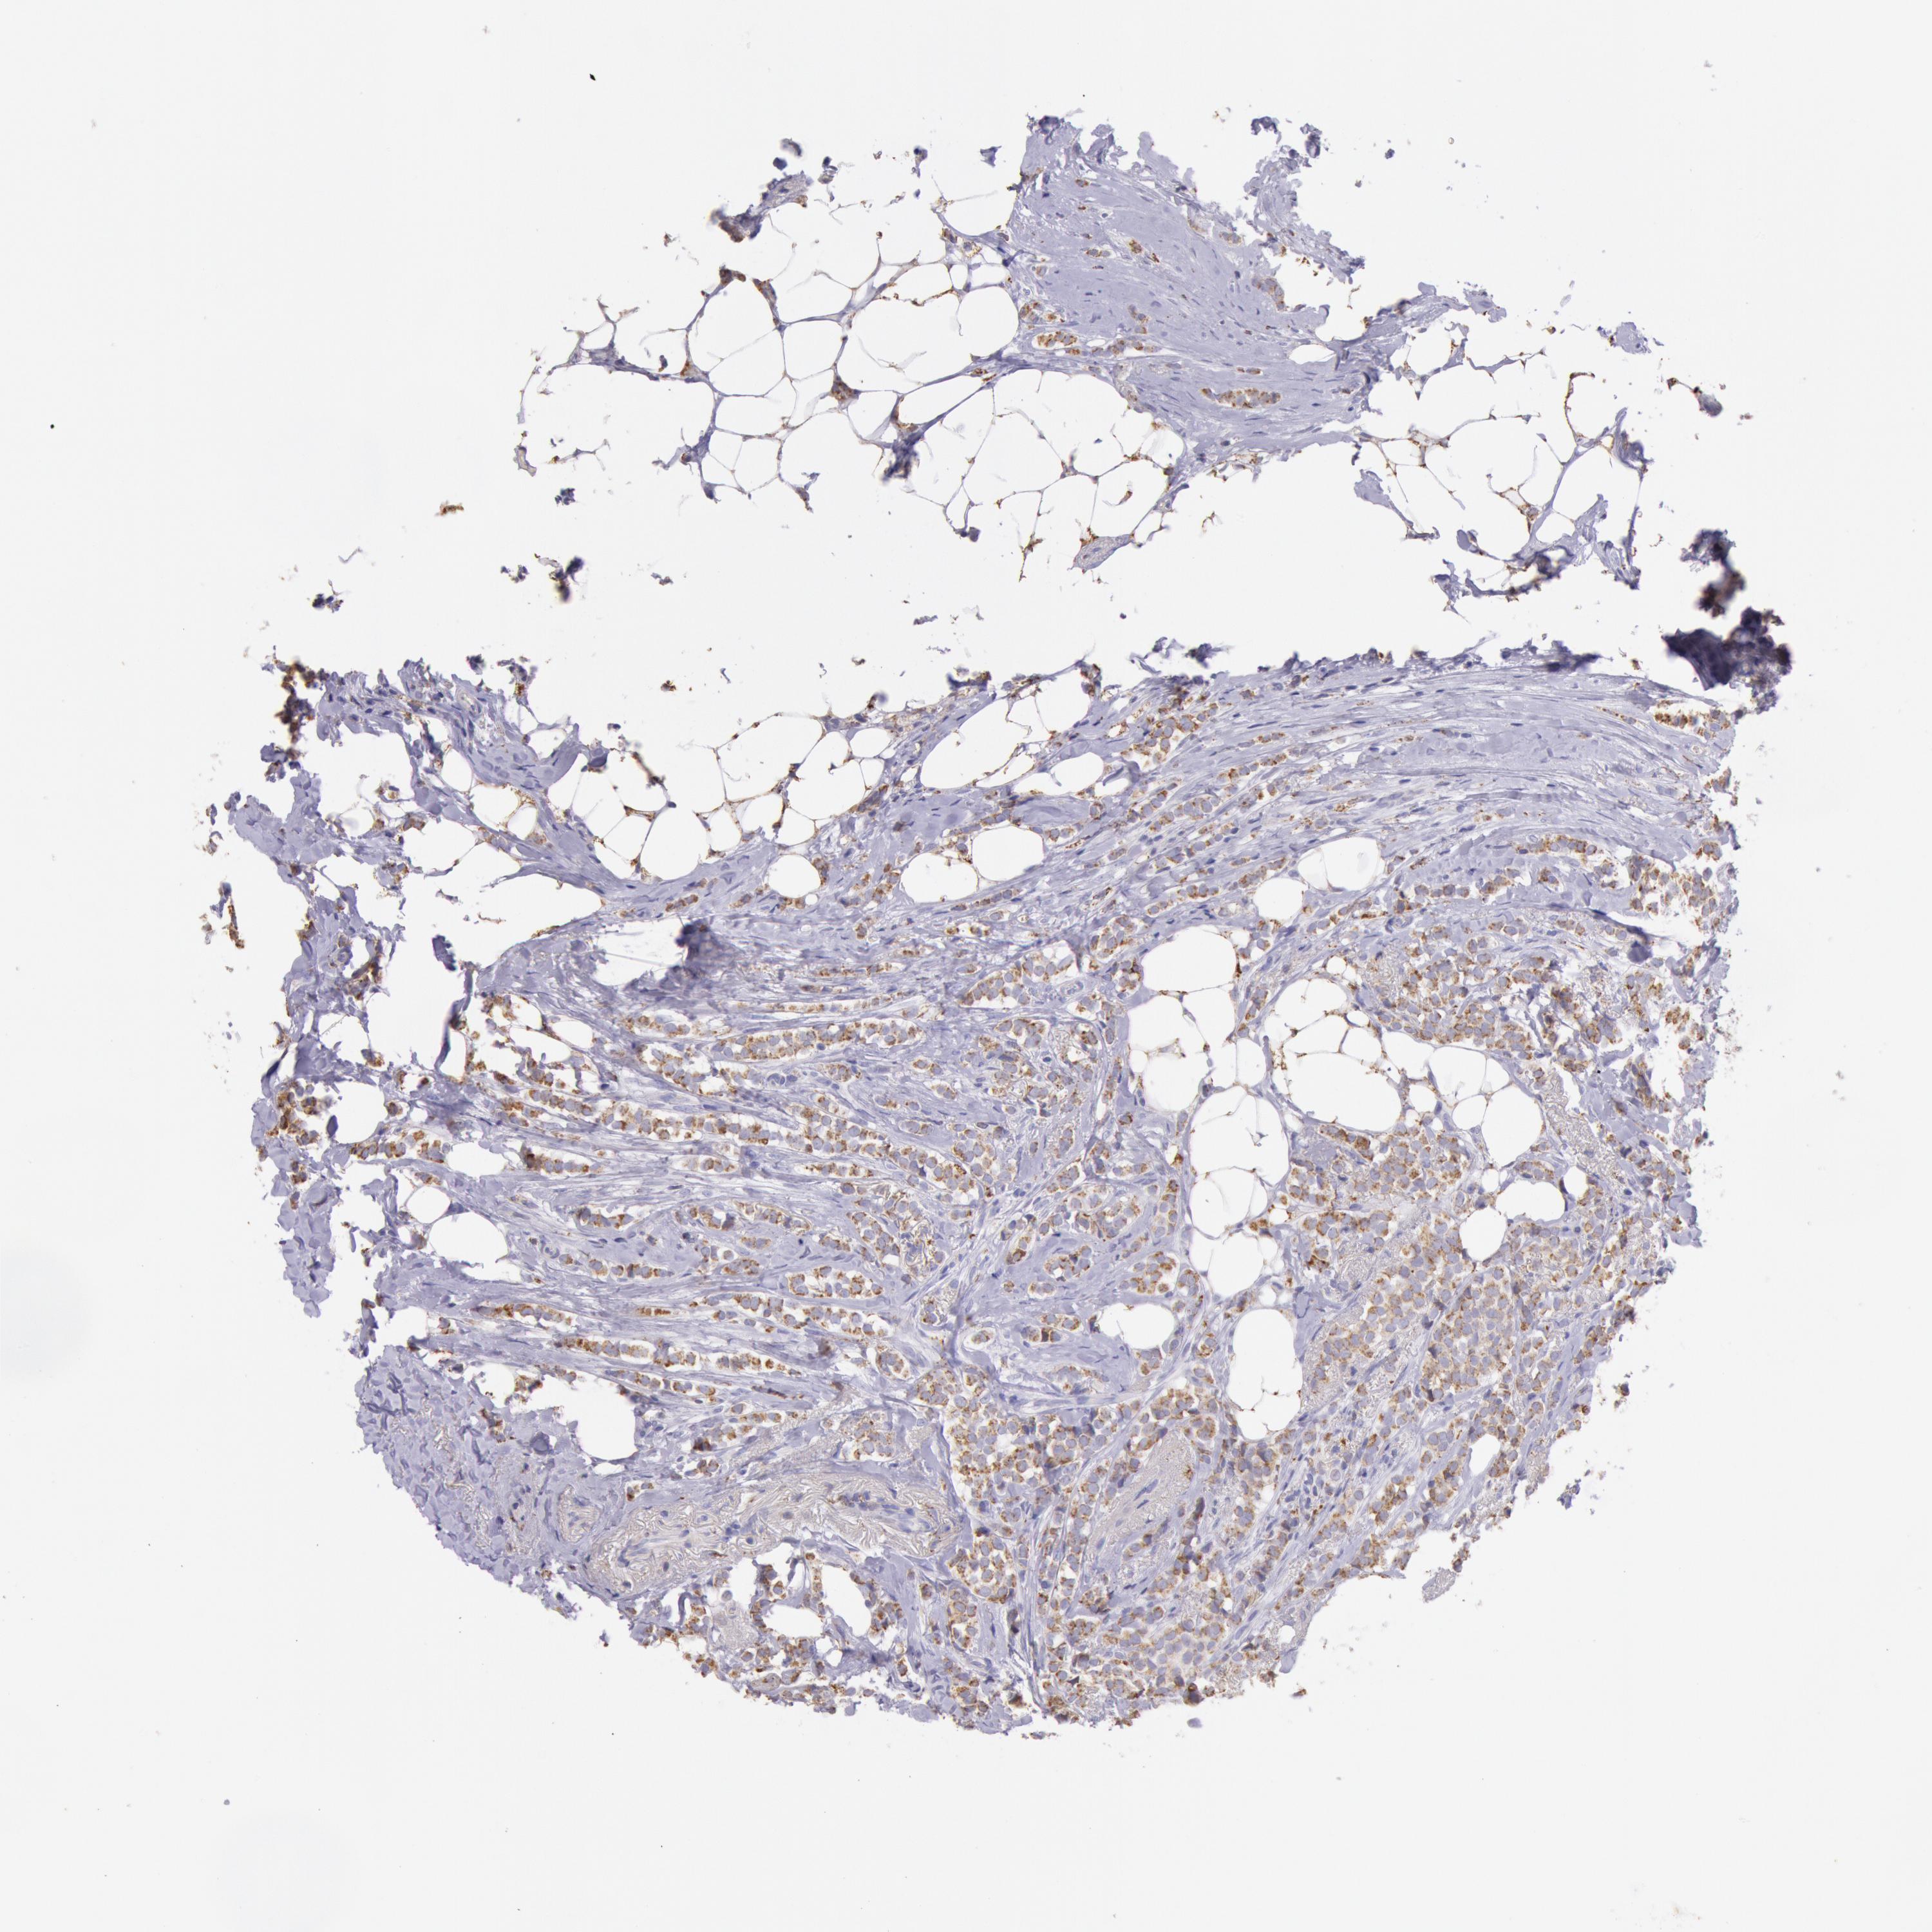

FRMD6

CANCER BREAST CANCER Show tissue menu

BRCA TCGA BRCA VALIDATION PROTEIN EXPRESSION

Breast cancer

Human cancer